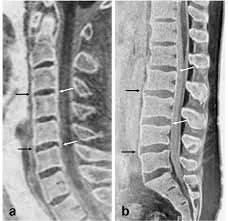

• Imaging modalties to evaluate pars stress fractures and stress reactions